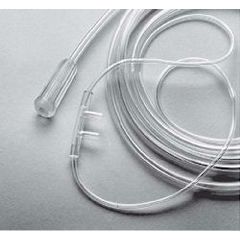

Oxygen Tubing and Accessories

Three-Channel Oxygen Supply Tubing - 50' - Case of 20 $105.97

Three-Channel Oxygen Supply Tubing - 7' - Three-Channel Oxygen Supply Tubing 7' - Case of 50 - Case of 50 $0.97

Oxygen 7´ Supply Tubing - Each $1.37

STAR LUMEN Oxygen Tubing with Connector and Lumen - 14' $2.07

Three-Channel Oxygen Supply Tubing $3.47 - $105.97